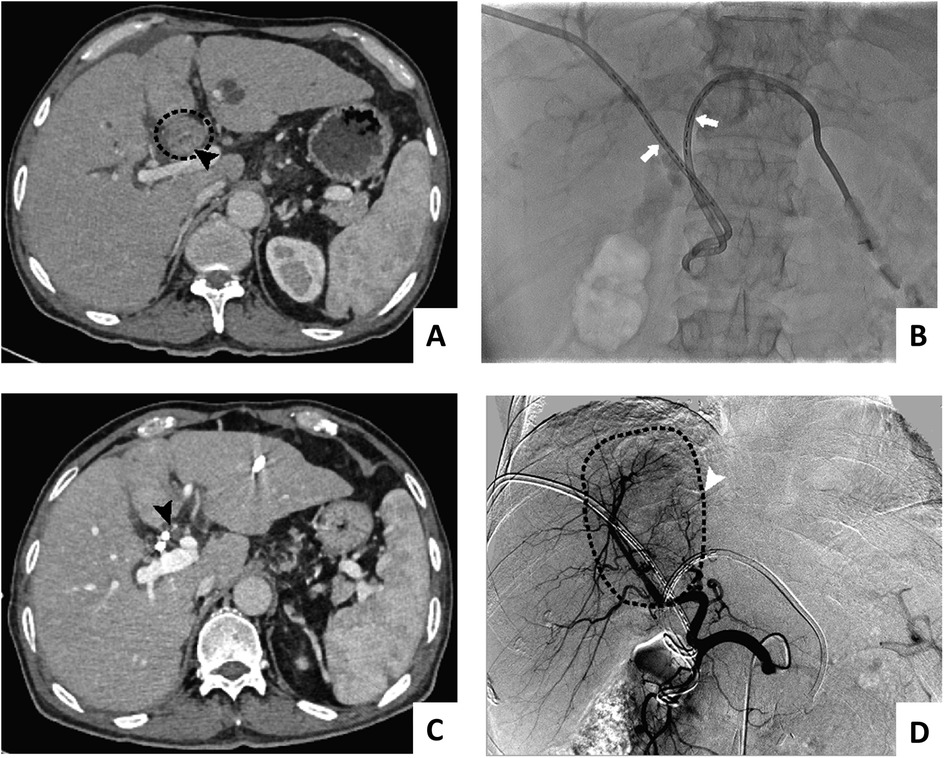

3. Biliary stenting combined with 125I seed implantation: a stent suitable for the diameter of the bile duct and the length of the obstructed segment and the long 6F sheath were placed side by side over the bile duct tumor; the stent was released first, and then the homemade 125I particles (PTBD tube plastic carrying 125I particles) were placed in parallel. The catheter with a soft inner core was trimmed to a suitable length for the bile duct tumor (the particle segment was 1 cm longer than the upper and lower ends of the bile duct tumor) and was delivered to the location of the bile duct tumor through the long sheath. Procedural and follow-up imaging of 125I stent-seed assembly was shown in Figure 1.

Figure 1. Procedural and follow-up imaging of 125I stent-seed assembly: pre-implantation (A), successful stent-seed implantation (B), 1-month follow-up imaging (projection 1) (C), 1-month follow-up imaging (projection 2) (D)